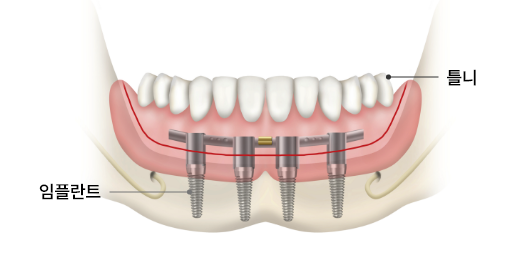

전악 임플란트 VS 임플란트 틀니

• 전악 임플란트

(임플란트 + 인공치아)

치아 착탈이 불가능하며, 자연치와 유사한 심미성과 기능성을 가지고 있습니다. 인공치아를 잡아주는 역할을 하며 임플란트 최대 개수는 위, 아래 각 12개 내외입니다.

• 임플란트 틀니

(임플란트 + 틀니)

임플란트 틀니는 임플란트를 잇몸뼈에 2~4개 정도만 식립한 후 연결장치에 맞게 틀니를 제작해 잇몸에 고정시켜 사용하게 하는 치료법입니다.